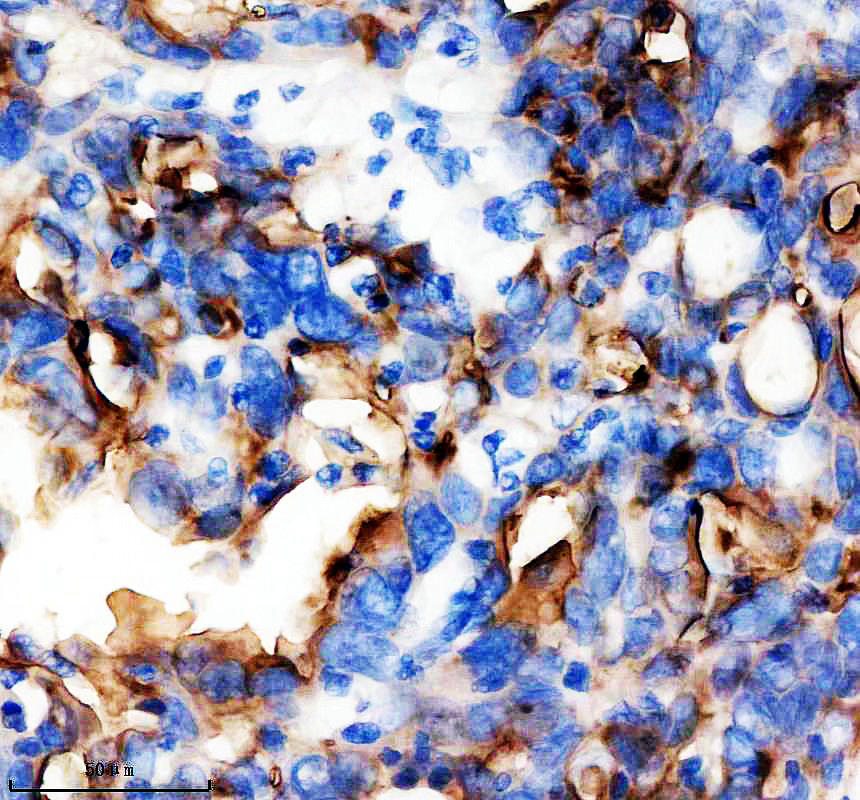

IHC analysis of MUC1 using anti-MUC1 antibody (BM4548).

MUC1 was detected in a paraffin-embedded section of human ovarian cnacer tissue. The tissue section was incubated with rabbit anti-MUC1 Antibody (BM4548) at a dilution of 1:200 and developed using HRP Conjugated Rabbit IgG Super Vision Assay Kit (Catalog # SV0002) with DAB (Catalog # AR1027) as the chromogen.